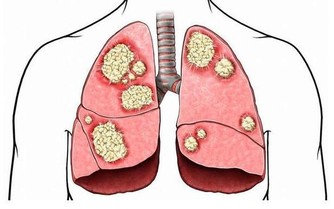

肝硬化等疾病,會造成靜脈的血液回流不通暢,也會讓肚臍周圍的血管曲張,而造成特殊的「海蛇頭」樣變化。